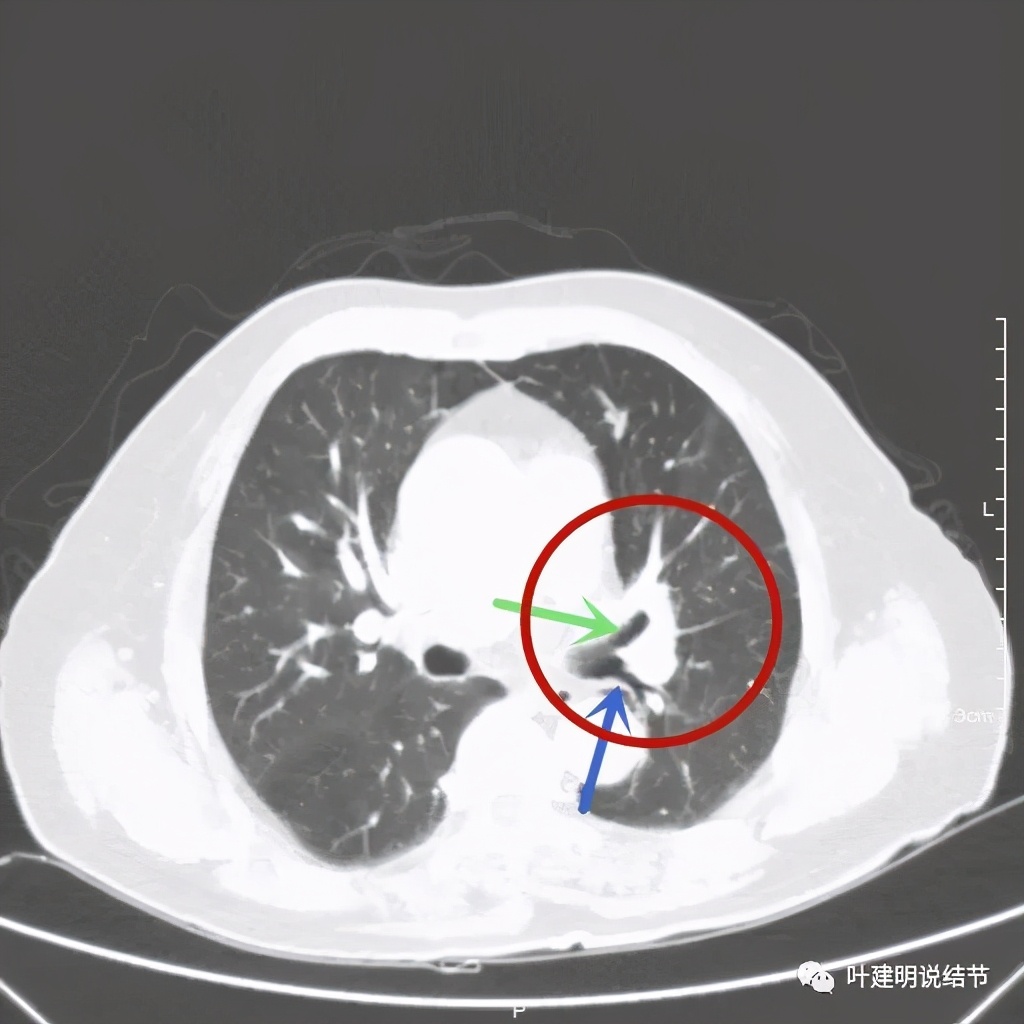

上图示肿瘤部位仍与肺动脉关系密切,似乎未能脱开,红色示肿瘤处

上图绿色示左上叶支气管,蓝色示下叶支气管开口处

我样的治疗效果,显然超出了我们之前的预期,那么接下来拟选择行手术治疗,初定左上叶袖式肺叶切除加淋巴结清扫,但因为肺门区仍有软组织影,与肺动脉的关系仍密切,肿瘤与肺动脉间能否游离开来还是未知数,但至少得努力争取,鉴于患者年纪虽大,肺功能指标尚可,血气分析也基本正常,所以与患方沟通后确定行手术探查,但也也说明有万一全肺切除的可能(虽然这种可能性较小)。